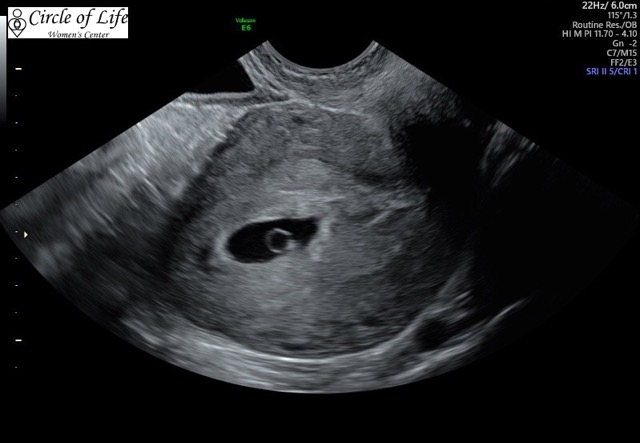

Transvaginal ultrasound WHICH SIDE IS THE TOP? Is the top of the picture where the wand is inserted??? Help